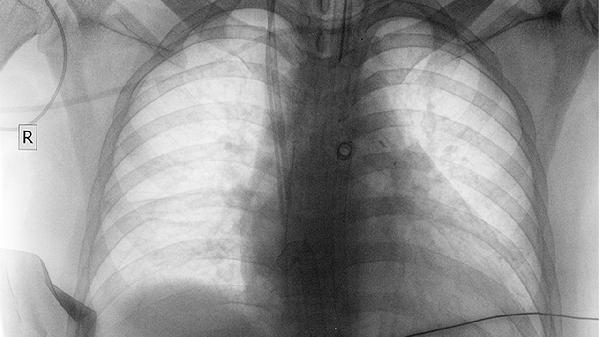

对于肿瘤放疗后出现的放射性肺炎,养阴清肺合剂能缓解咳嗽胸痛症状。放疗导致肺泡上皮损伤,引发渗出性炎症。合剂中的白芍、薄荷脑具有抗炎镇痛作用,常与复方鲜竹沥液、乙酰半胱氨酸颗粒联用。患者需定期复查胸部CT评估疗效。